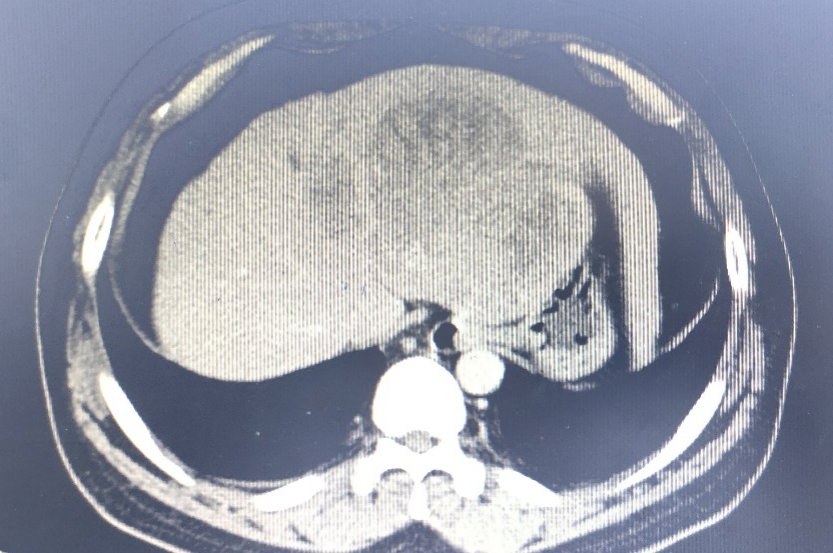

病例:患者男性,37岁,主因上腹部憋胀疼痛1月余在中国医学科学院肿瘤医院诊断为“原发性肝癌”,未行治疗。近日上腹部疼痛明显加重,伴有不思饮食,来我院就诊,住入普外科三病区。入院检查:腹部CT:肝左叶团块状软组织影,大小约12×11 cm,腹腔可见多发肿大淋巴结。AFP:>1210ng/ml。

为什么要用到微导管精细介入  精准栓塞——微导管肝动脉灌注化疗栓塞术给肝癌患者带来希望!_https://www.jmylbn.com_新闻资讯_第1张CT影像

经过严密的病情分析和风险评估,诊断为:原发性肝癌 Ⅲb期,肝功能Child-Pugh  B级。目前暂时无法手术治疗,拟行经导管肝动脉灌注化疗栓塞术(TACE),但患者肝脏肿瘤瘤体巨大,周围血管受肿瘤压迫,迂曲明显,普通导管难以直达病灶,且患者BMI偏高,双侧股动脉触诊不明确,手术难度明显增加。放射科副主任医师张新异详细阅片,细致查体,并与患者及家属耐心解释沟通后,决定为患者行经导管肝动脉灌注化疗栓塞术(TACE)。6月29日,张新异在介入放射科为患者成功实施TACE手术,术中采用微导管通过迂曲的肝动脉,直达肿瘤,减少了对正常肝脏的副损伤,大大缩短了术后恢复的时间。手术过程顺利,术中及术后患者无明显不适,手术当天即可下床行走。